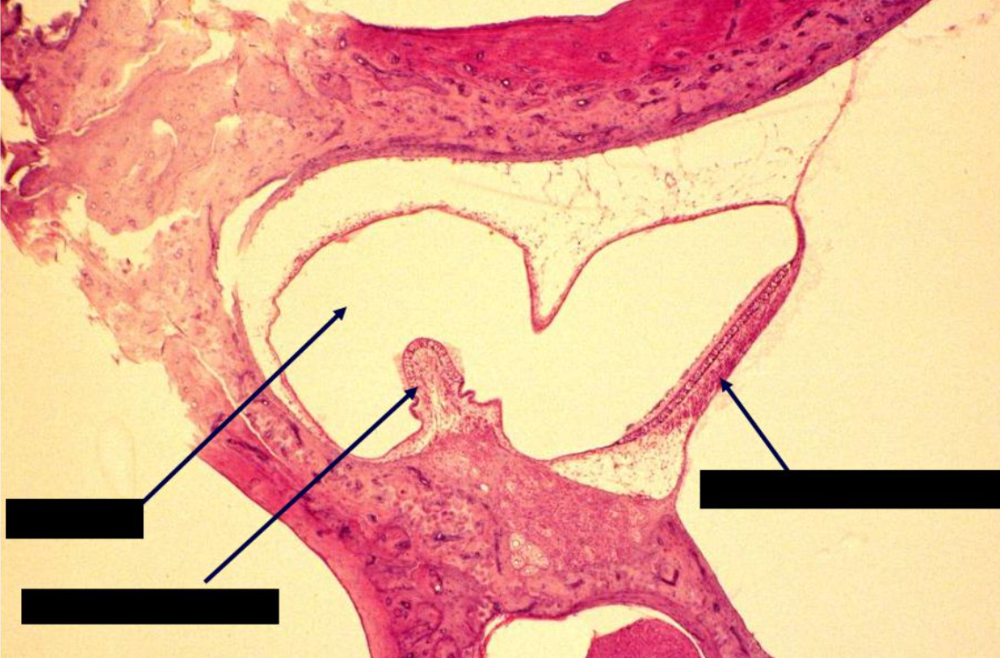

What is 5?

auricle

37

The lateral ______ of the external auditory meatus is ______, while the medial ______ is made of ______ from the ______ bone.

one-third, cartilaginous, two-thirds, bone, temporal

38

The lateral part of the external auditory meatus is lined by skin containing ______, ______ glands, and ______ glands, which are modified ______ ______ glands that secrete ______.

hairs, sebaceous, ceruminous, apocrine sweat, cerumen

39